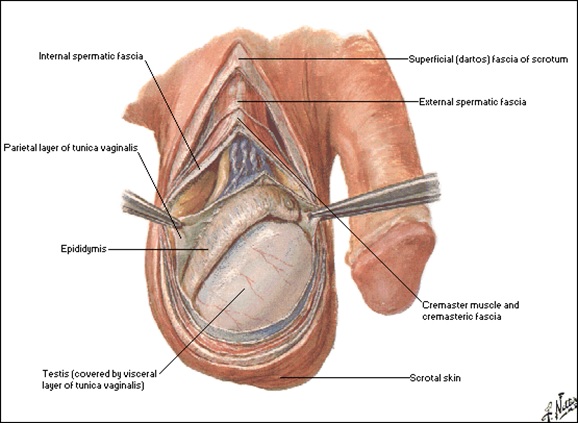

Scrotul

Bursele scrotale sunt formaţiuni cutanate şi fibromusculare ce protejează gonadele şi regleză temperatura lor.

Sunt alcătuite din mai multe învelişuri ce continuă planurile pereteluui abdominal:

- piele;

- Dartos;

- Fascia spermatică externă;

- fascia cremasterică;

- fascia spermatică internă;

- vaginala.

Scrotul şi conţinutul scrotal, vedere laterală:

Testiculul

Dimensiuni: 4x3x2,5 cm, formă ovoidă, 20-25 g.

Structură:

- a exterior-albugineea: trimite septuri conjunctivo-vasculare în parenchim, delimitând 200-300 lobuli

- fiecare lobul conţine 1-4 tubi seminiferi ce converg în mediastinul testicular si se unesc cu canalele eferente

Vascularizaţie:

Arterială:

- a. testiculară (r. din aorta abd.)

- a. deferenţială (r. din a. vezicală inf.)

- a. spermatică ext. )r. din a. epigastrică inf.)

Venoasă:

- vv. testiculare şi epididimare ce se anastomozează formând plexul pampiniform dispus ant. şi post. de funicul® v.testiculară

Testicul, epididim si duct deferent: